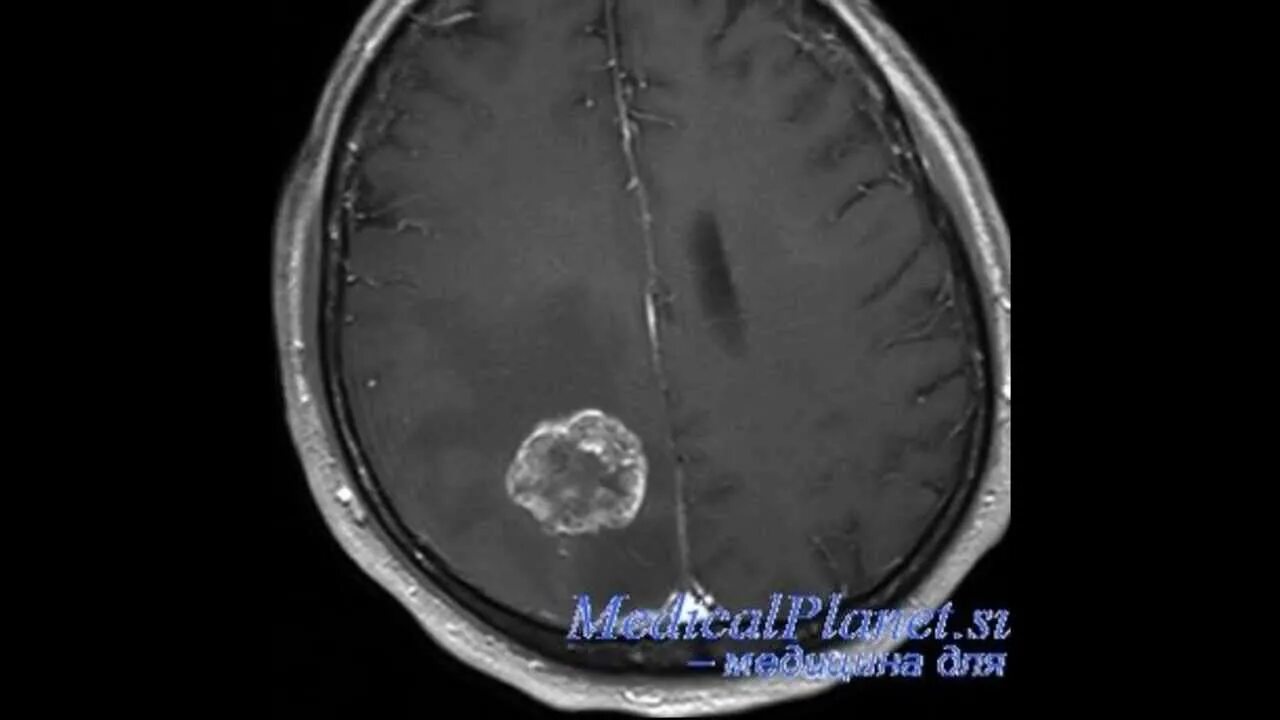

Как умирают от рака головного мозга